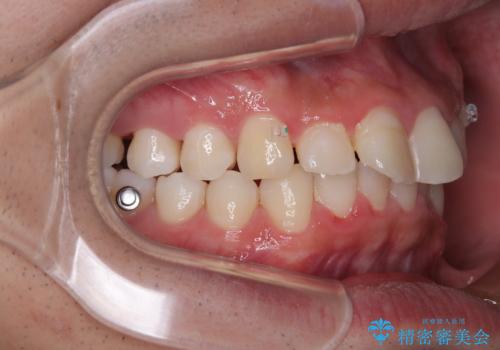

インビザラインによる矯正治療をご希望でしたが、上顎歯列の前方位と鋏状咬合を確実に改善することを目的として、補助装置を併用することとしました。

補助装置を併用せずに治療を終える可能性はありましたが、確実に結果を得るために補助装置を活用しました。

イメージしたとおりの仕上がりとなりました。